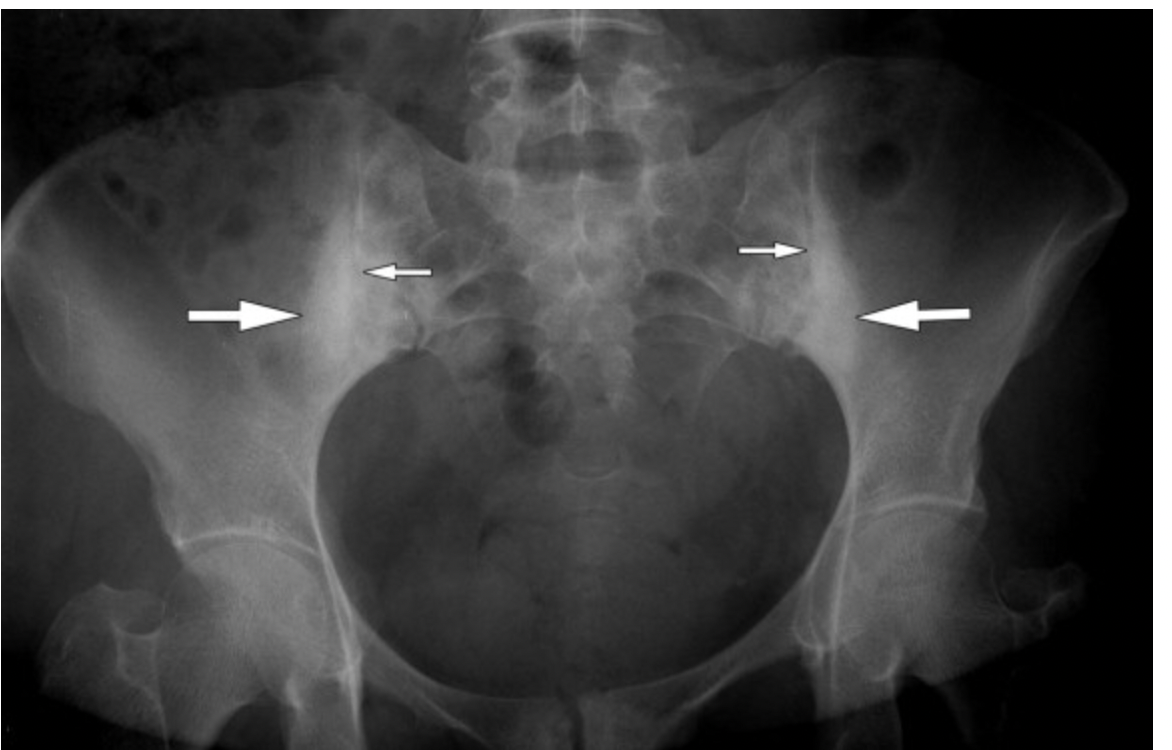

Sacrolititis

Ankylosing spondylitis